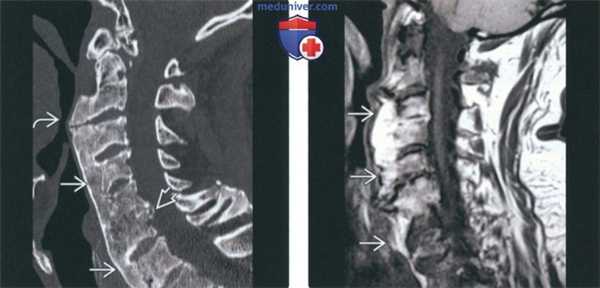

(Слева) На сагиттальной КТ определяется массивная оссификация ППС с деформацией гортаноглотки. Оссификация при ДИСГ обычно локализована ниже осевого позвонка, но может достигать его уровня. Длительная иммобилизация стала причиной анкилоза на уровне С5-С6. Вторичный остеоартроз, не связанный с ДИСГ, определяется на уровне С1-С2.

(Справа) На сагиттальной МРТ (Т1 ВИ) определяется массивная передняя оссификация, сопоставимая с ДИСГ. Жировой костный мозг соотносится с гиперинтенсивным Т1 сигналом в переднем оссификате.

(Справа) МРТ, сагиттальная проекция, режим Т2 с подавлением сигнала от жира: у этого же пациента подтверждается наличие переднего костного образования, содержащего костный мозг. Тем не менее, дополнительно визуализируется грыжевое выпячивание диска на уровне CS-C6, которое является причиной боли в шейном отделе. Для ДИСГ не характерно наличие выраженного болевого синдрома, поэтому следует осуществить поиск других его причин. Патологические изменения диска и перелом с псевдоартрозом могут являться этиологическими факторами развития радикулопатии или миелопатии. Дисфагия является результатом формирования костного образования спереди. (Слева) МРТ, сагиттальная проекция, режим Т1. признаки ДИСГ. Исследование выполнено в правой парасагиттальной проекции. Передняя наплывающая оссификация выражена здесь в гораздо большей степени, нежели слева (не показано). Переднее костное образование берет начало непосредственно из центра тел нескольких позвонков и из нижнего и верхнею отделов тел других позвонков. И то и другое характерно для данною заболевания. Диски, а также дугоотростчатые суставы остаются неизмененными. ДИСГ не является истинной артропатией, однако в ряде случаев сочетается с дегенеративным поражением позвоночника.